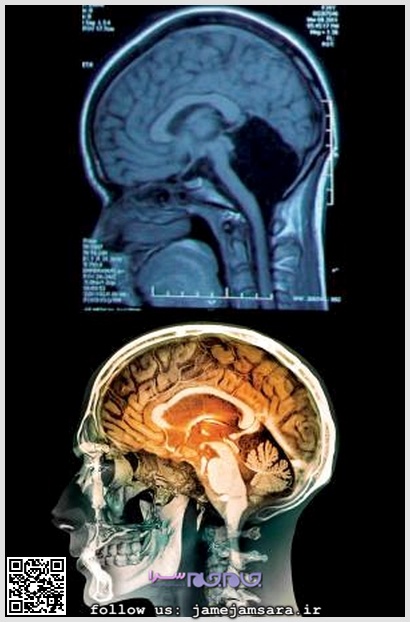

حفره خالی مخچه زن چینی در تصویر مشخص است

مخچه که از آن به عنوان مغز کوچک نیز یاد میشود، بخش کوچکی از پشت جمجمه را به خود اختصاص داده و نیمی از نورونهای مغزی را در خود گنجانده است. وظیفه مخچه را میتوان در یادگیری، تلفظ کلمات و حرکات دانست. پزشکان معتقدند نداشتن مخچه میتواند با بیماریهای بسیاری مانند عقب ماندگی ذهنی، حرکتی یا سایر وظایف و عملکردهای مهم مغزی روبرو شود.